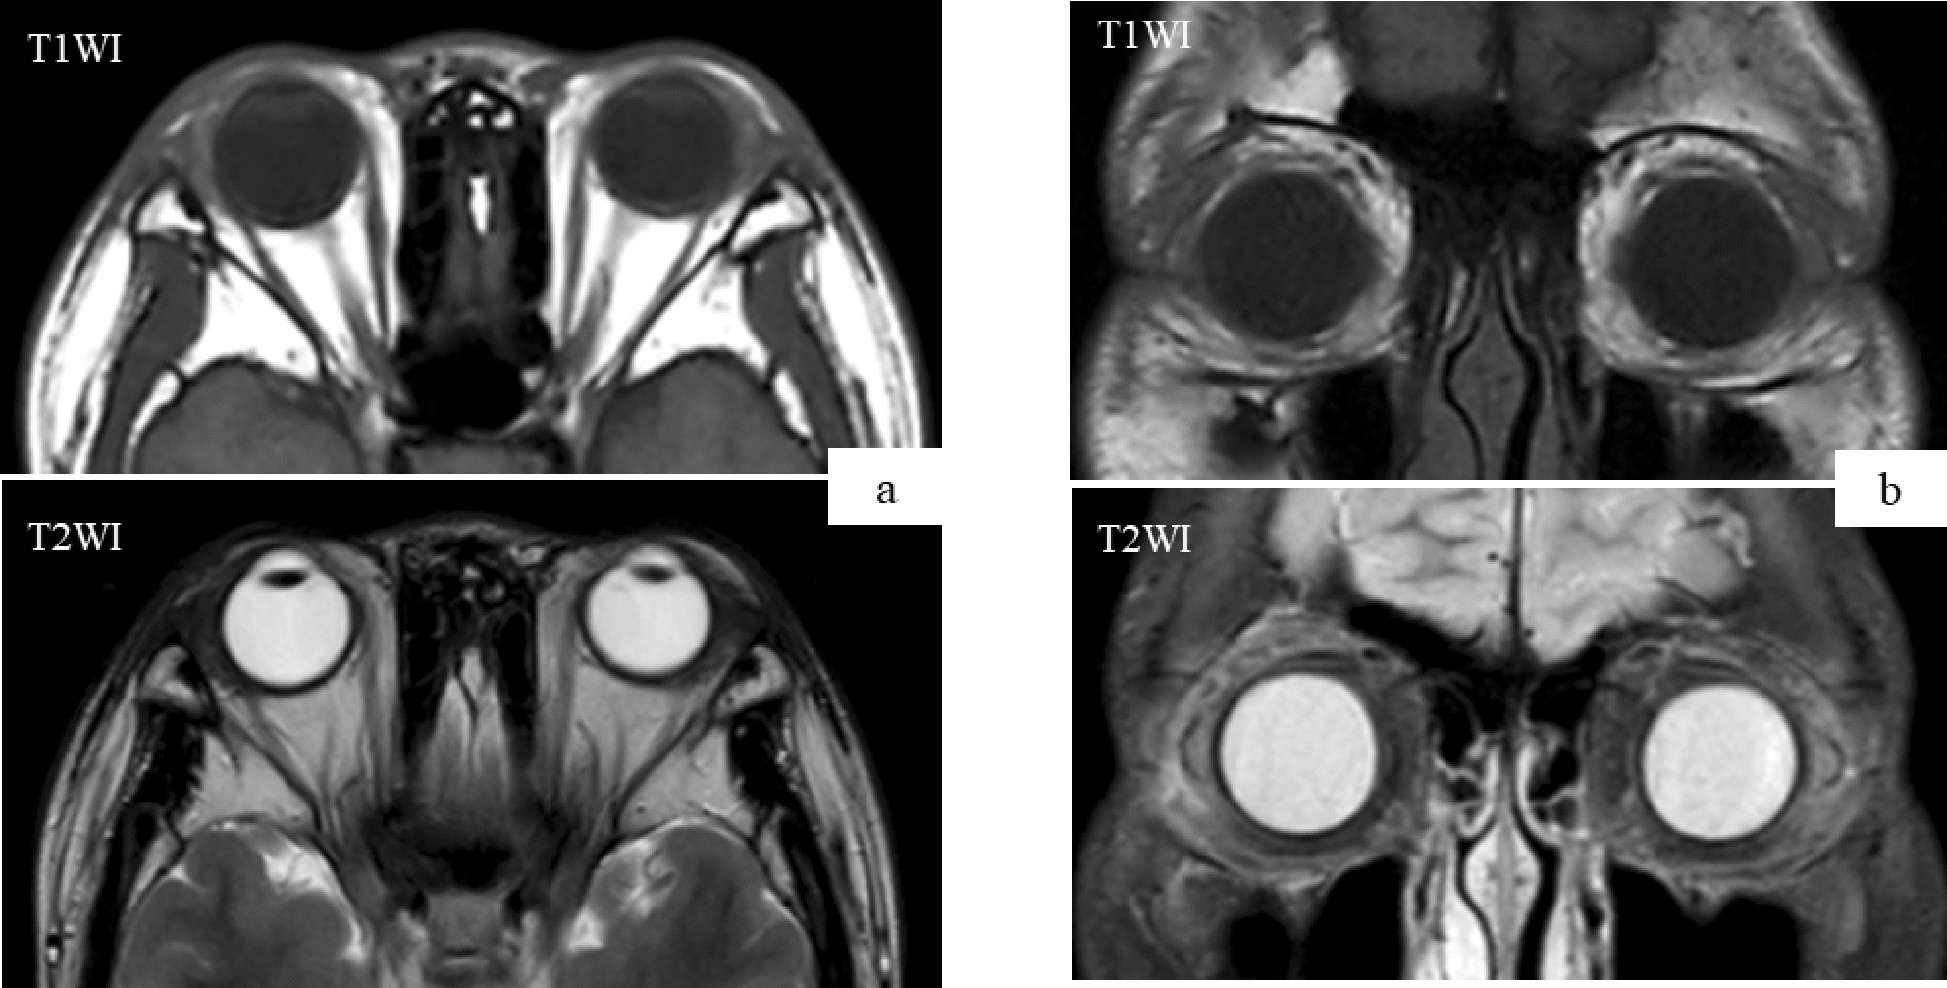

Magnetic resonance imaging (after second operation). a, b Axial and coronal MRI demonstrated no presence of an enhanced lesion of the bilateral lacrimal gland